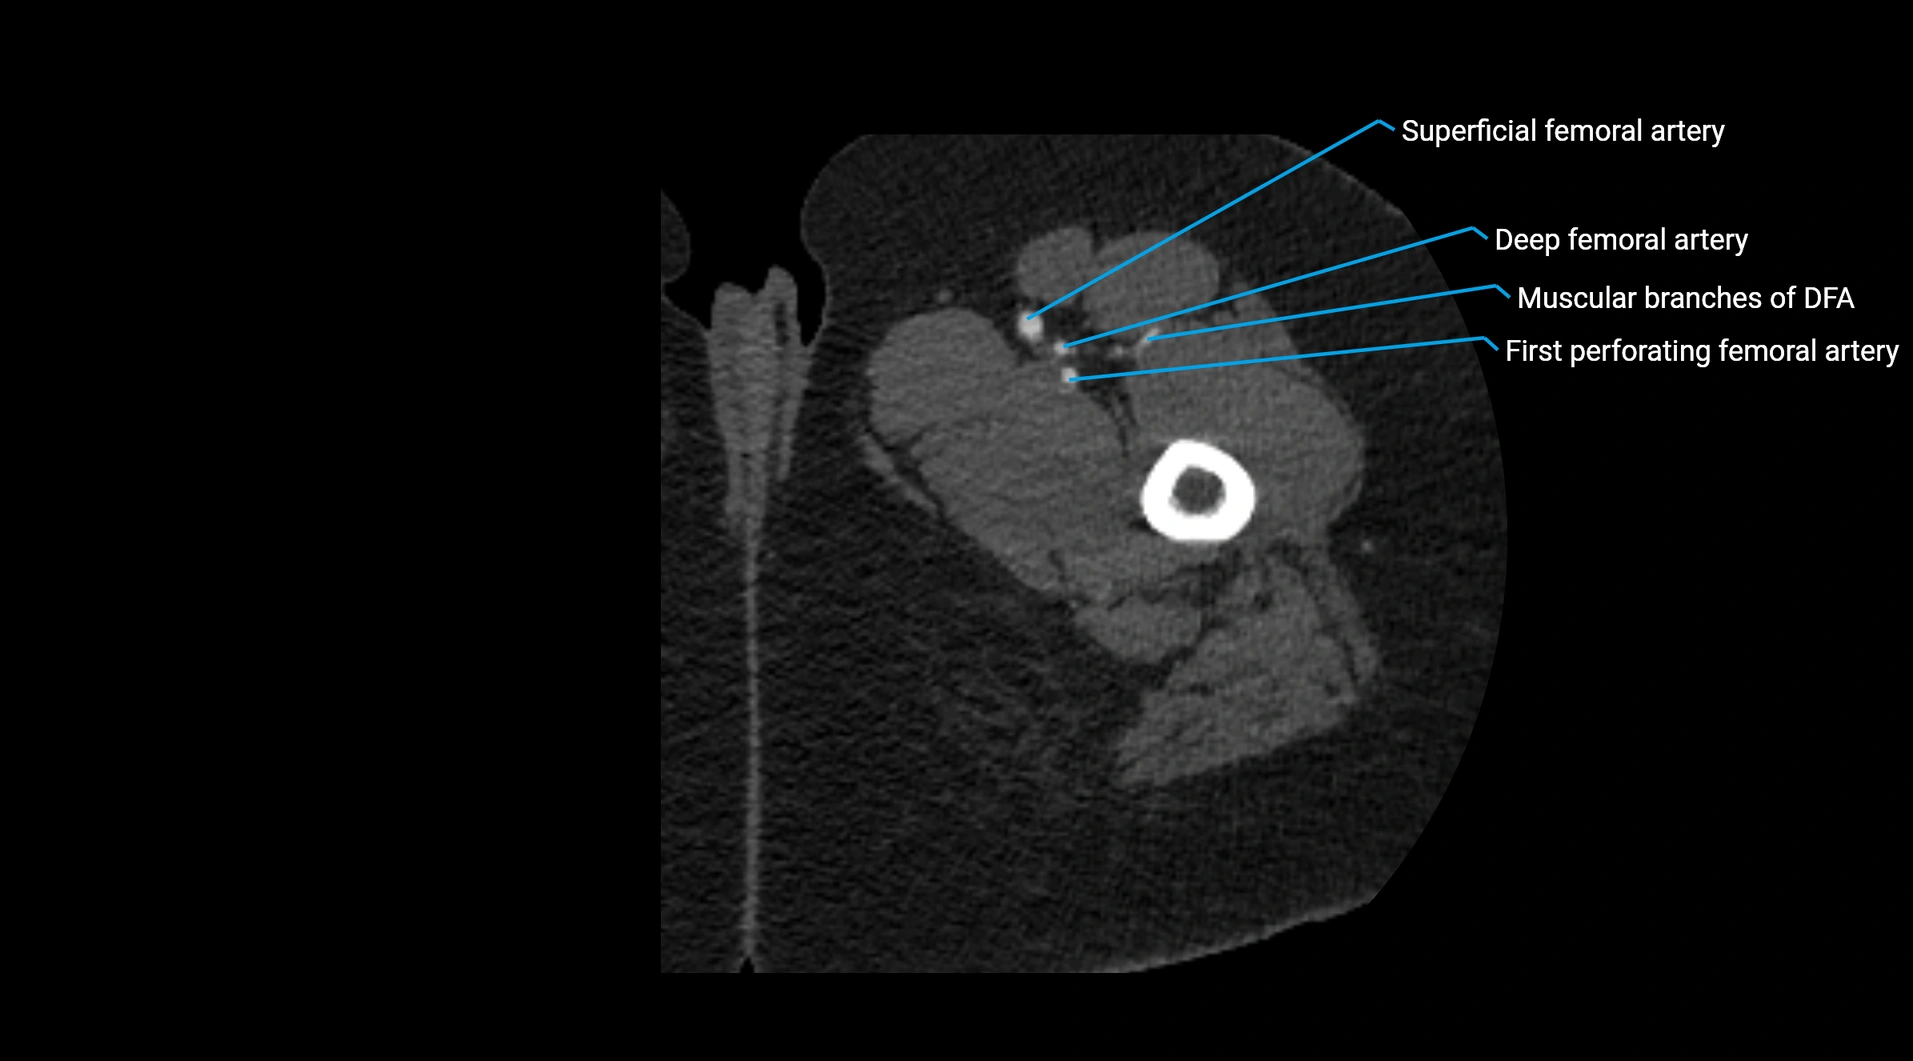

CT images

image

Contrast-enhanced CT (CTA):

• Gold standard for abdominal aortic imaging

• Provides excellent detail of lumen, wall, aneurysm, thrombus, and branch vessels

• Multiplanar and 3D reconstructions help in aneurysm measurement, stent graft planning, and dissection evaluation